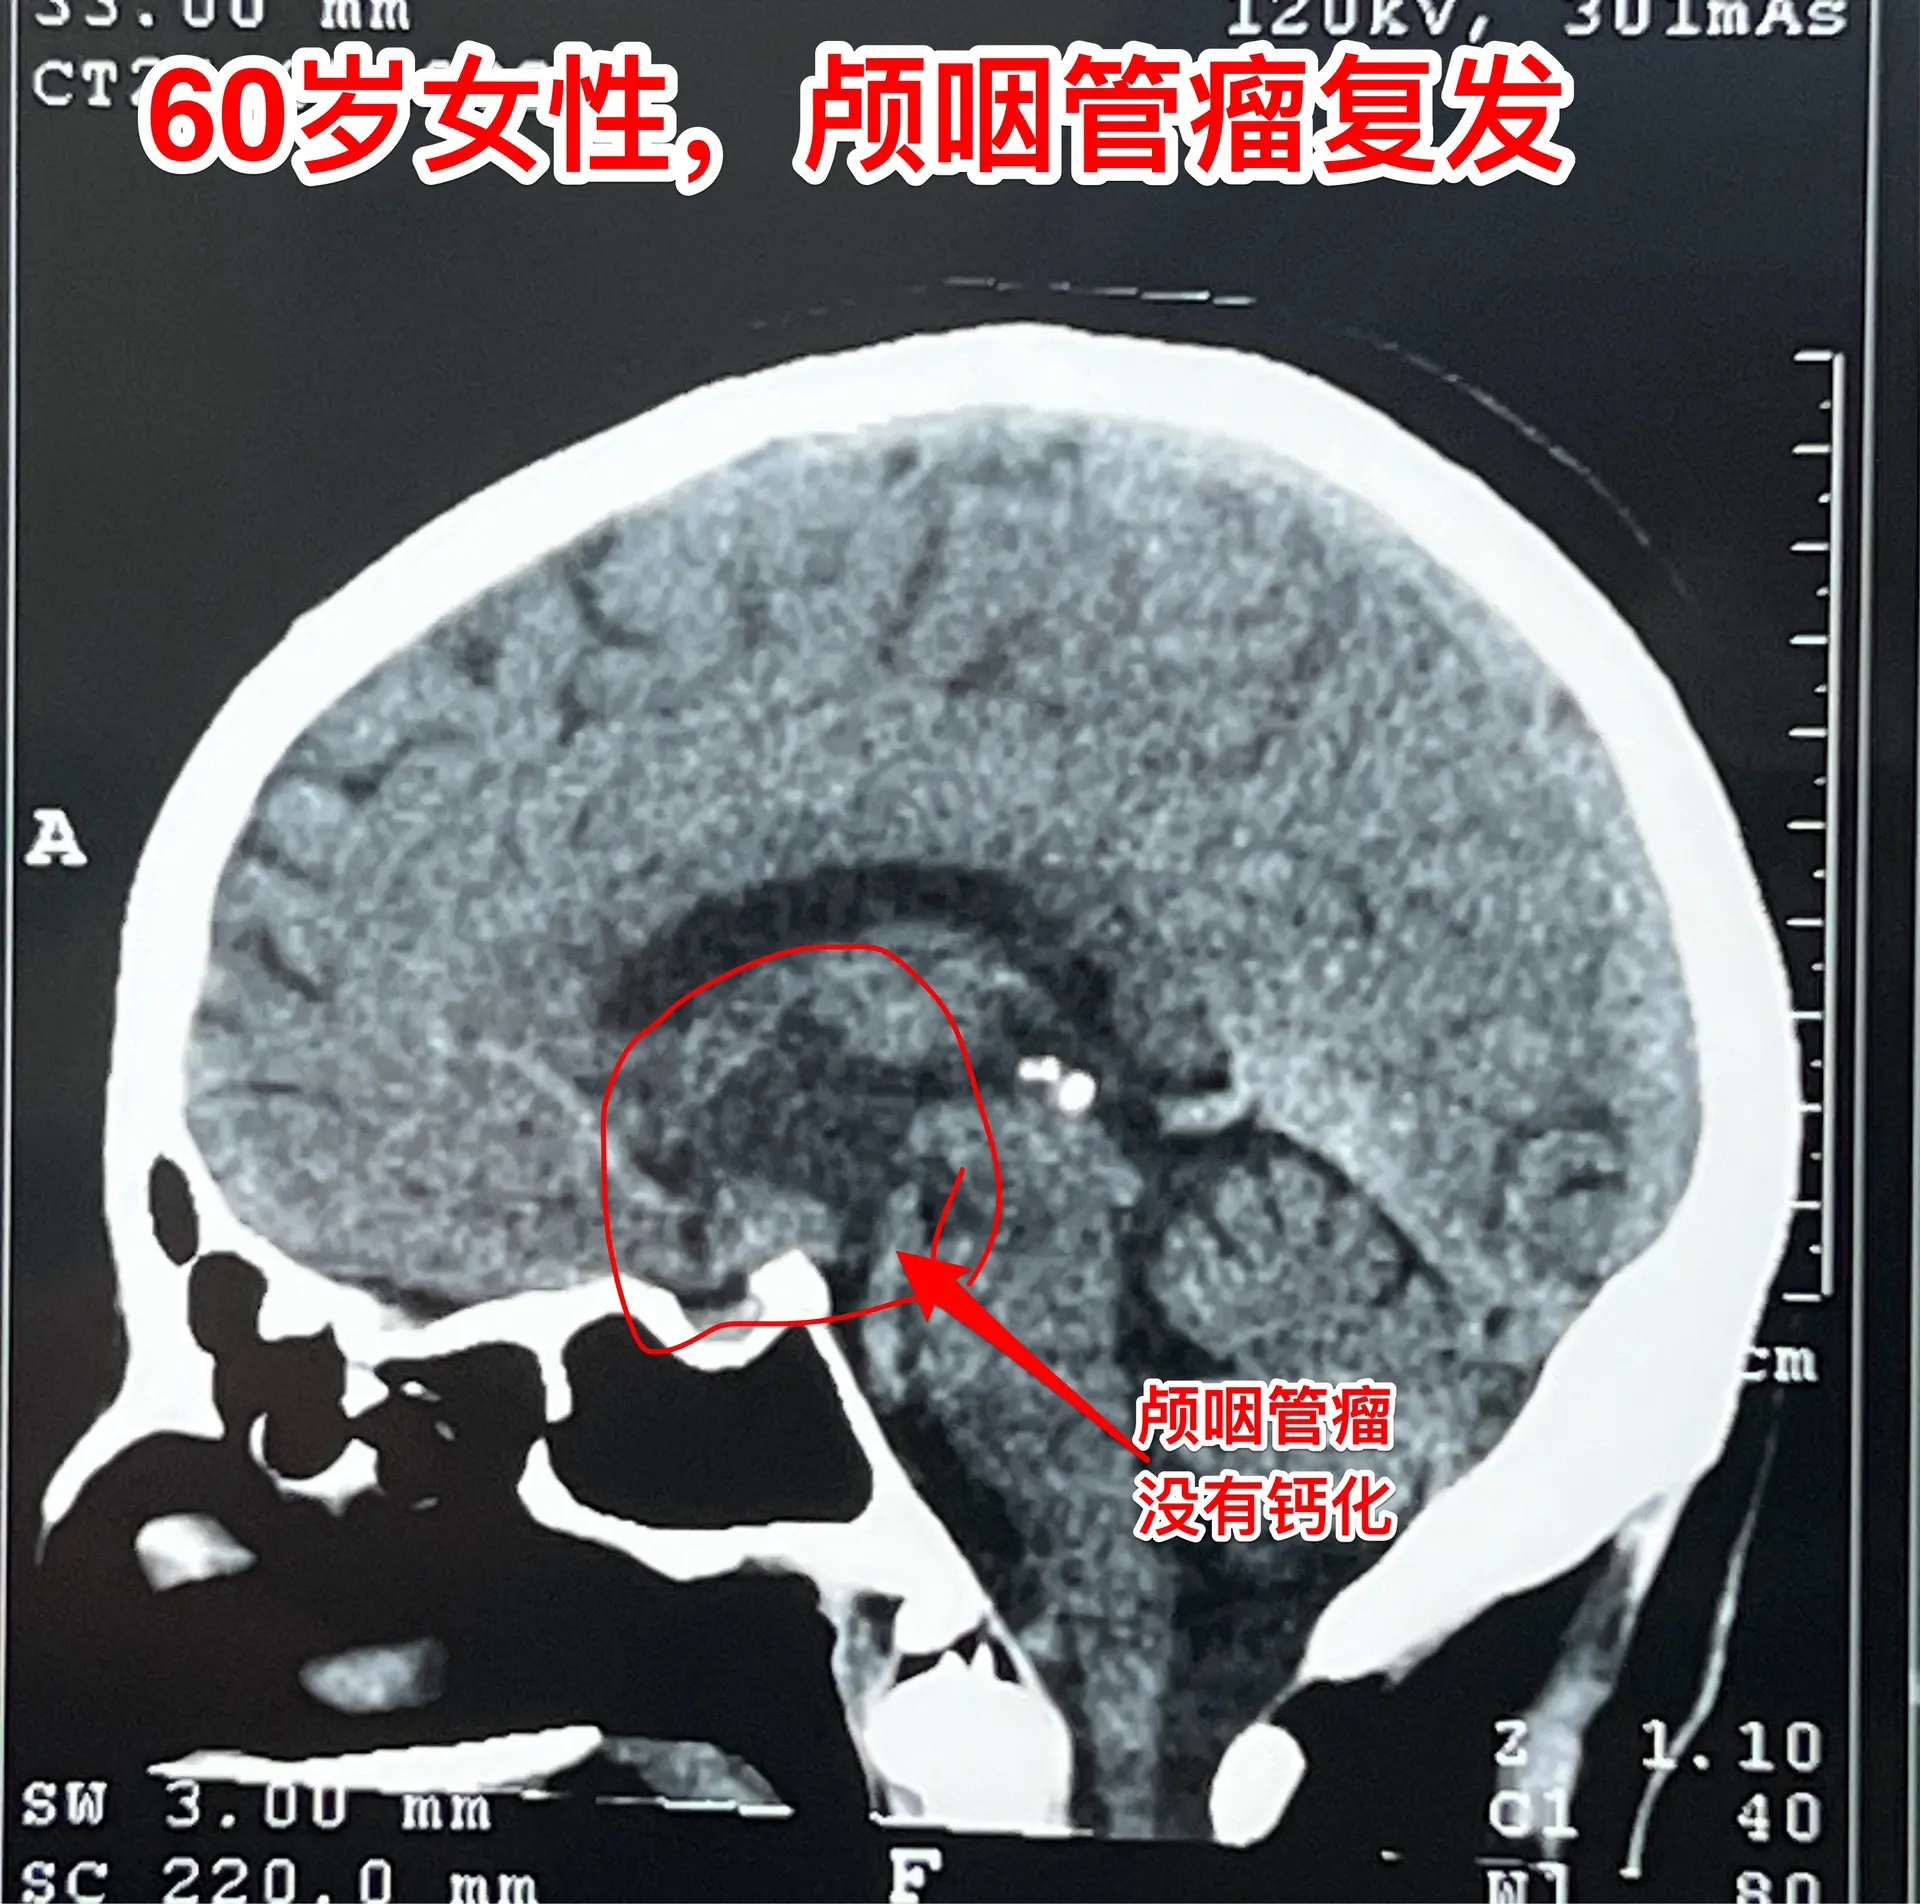

60岁连云港市的老人视力下降⬇️。老人自幼右眼受伤了,右眼视力属于无效视力,几十年内完全靠左眼来维持视力,能正常作事儿。 一年半前老人感到左眼视力下降了,到医院去检查,发现脑部长了颅咽管瘤。准备作手术治疗,在手术前作肺部CT的时候却意外发现肺部长了肿瘤,怀疑是肺癌,考虑到肺癌是恶性肿瘤,而颅咽管瘤是良性肿瘤,所以就先作肺癌切除术。肺癌手术后三个月又作了开颅手术,切除颅咽管瘤,手术后左眼视力有好转。 一个人居然同时长了两种肿瘤!真是祸不单行! 今年九月份患者左眼视力又出现下降,快失明了。在当地医院复查磁共振显示肿瘤复发了,十月份来我科住院。10月31日作了开颅手术,将颅咽管瘤切除了。手术后老人说视力有好转。